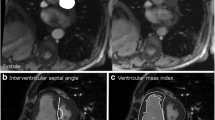

Measurements of the LV dimensions (interventricular septal diameter in diastole (IVSd) and diastolic LV posterior wall thickness (LVPWD)) were measured in the parasternal long-axis view.

The LV mass index (LVMI) was calculated from these linear measurements. LV ejection fraction (LVEF) was calculated using the modified Simpson’s biplane method from the apical 4- and 2-chamber views. IVC diameter was measured in the subcostal view. Mitral inflow velocities (E, A, E/A, E-wave deceleration time) were assessed using pulsed-wave Doppler from the apical 4-chamber view at the level of the mitral valve leaflet tips. Pulsed-wave tissue Doppler imaging was used to measure early relaxation velocity (e´). The LA end-systolic volume was measured by the biplane area-length method and indexed to body surface area (BSA) to acquire the LA volume index (LAVI). Tricuspid annular systolic plane excursion (TAPSE) was measured by M-mode as the longitudinal displacement of the lateral tricuspid annulus during systole. RV end-diastolic and end-systolic areas were measured in the apical view by tracing the RV endocardium in systole and diastole. Fractional area change (FAC) was calculated as the difference between RV end-diastolic area and the end-systolic area. The tricuspid regurgitation (TR) peak velocity was measured as the peak velocity of the TR jet using CW Doppler, identified either in the parasternal short-axis view or apical 4-chamber view with the help of color Doppler. TR maximal pressure gradient (TR max PG) was calculated from the pulmonary regurgitation velocity. Speckle tracking echocardiography of the LV was performed in the apical 4-chamber, 2-chamber, and apical long-axis view to acquire the global longitudinal strain (GLS). Analyses were performed by placing two points at the basal level and one point at the apex after which the automated software generated a region of interest that covered the LV wall. Segments with persistent inadequate tracking were excluded from analysis and GLS was calculated by averaging values measured in the remaining segments. RV speckle tracking was performed in the apical 4-chamber view by manual delineation of the endocardial border of the RV myocardial wall [11]. RV free wall longitudinal strain (RVFWS) was calculated as the mean of the RV lateral wall segments.

Unadjusted continuous correlations between the subsegmental vessel fraction and echocardiographic parameters are shown in Fig. 2a-h.

2A-D depicts the relationship between subsegmental vessel fraction and (A) IVSd (B) IVC diameter, (C) TAPSE, (D) LVMI. Figure 2E-H depicts the relationship between segmental vessel fraction and (E) LVPWD, (F) IVSd, (G) IVC diameter, (H) TR max PG

(A) with subsegmental vessel fraction was negatively correlated IVSd, (B) subsegmental vessel fraction was negatively correlated with IVC diameter, (C) subsegmental vessel fraction was negatively correlated with TAPSE, (D) subsegmental vessel fraction was positively correlated with LVMI, (E) segmental vessel fraction was positively correlated with LVPWD, (F) segmental vessel fraction was positively correlated with IVSd, (G) segmental vessel fraction was positively correlated with IVC diameter, (H) segmental vessel fraction was positively correlated with TR max PG.

IVC inferior vena cava,

IVSd interventricular septal thickness in diastole

LVEDVi left ventricular end-diastolic volume index

LVMI left ventricular mass index

LVPWD left ventricular posterior wall dimensions

RVFWS right ventricular free wall longitudinal strain

TAPSE tricuspid annular plane systolic excursion

TR max PG tricuspid regurgitation tricuspid maximal pressure gradient